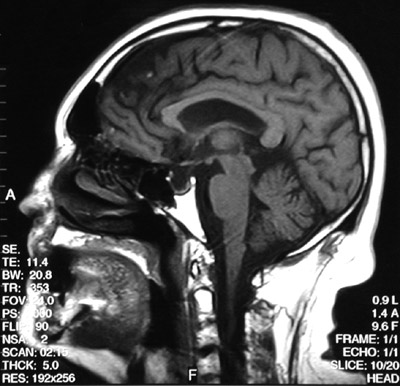

| The T1 weighted MRI scan in sagittal view above demonstrates an empty sella turcica. A T1 weighted post gadolinium coronal view is seen below. Some cases of empty sella syndrome may result from a herniation of the arachnoid through the diaphragma sella to cause pressure atrophy of the pituitary. |